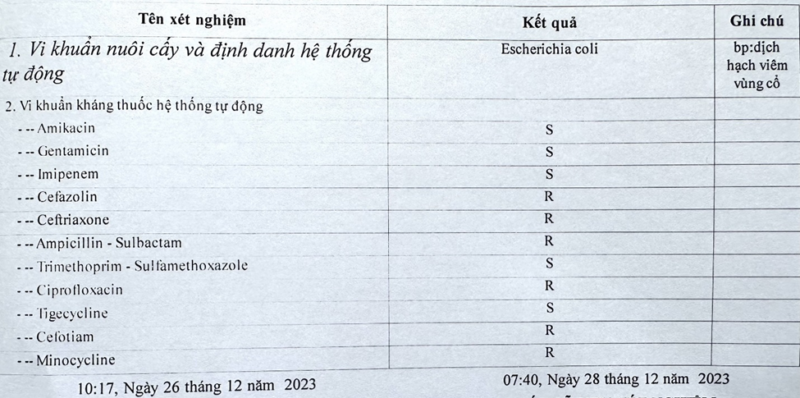

+ Lấy dịch mủ vùng cổ nuôi cấy cho kết quả Escherichia Coli

Hình 5. Kết quả kháng sinh đồ của bệnh nhân

Sau mổ bệnh nhân được điều trị tích cực, tiếp tục sử dụng kháng sinh theo kháng sinh đồ, thay băng bơm rửa 2 lần/ngày, khi lượng dịch mủ giảm, tiến hành khâu thưa khép dần vết mổ tránh thiếu da khi hết viêm. Điều trị tích cực sau mổ 20 ngày, bệnh nhân ổn định, hết viêm, đủ điều kiện xuất viện. Khi ra viện bệnh nhân được kê đơn ngoại trú uống kháng sinh Costrimstada (Trimethoprim và Sulfamethoxazole) 1 tháng tiếp theo, thay băng hàng ngày cho đến khi cắt hết chỉ. Hiện nay bệnh nhân đã phục hồi hoàn toàn.

Bệnh nhân được báo cáo ở đây có biểu hiện tăng số lượng bạch cầu trung tính với chỉ số bạch cầu 22,07 G/L (N 87,08%), cao nhất là 33,34 G/L (N 77,7%). Hệ vi sinh vật hội sinh của khoang miệng rất phong phú. Một số vi khuẩn có liên quan đến sự xuất hiện của viêm tấy lan tỏa. Nhiễm trùng có thể là do nhiều vi khuẩn cùng một lúc hoặc chỉ có một mầm bệnh được tìm thấy. Trong nghiên cứu của mình, Kouassi và cộng sự tìm thấy vi khuẩn hiếu khí (19%), vi khuẩn kỵ khí (45%) và vi khuẩn kỵ khí tuyệt đối (36%). Streptococci là loại vi khuẩn kỵ khí thường gặp nhất (64,1%) và Prevotella sp (55%) trong số các vi khuẩn kỵ khí [3], [11]. Liên cầu β tán huyết nhóm A và Prevotella là những loại thường gặp. Các vi khuẩn khác như Pseudomonas aeruginosa , Staphyloccus, Escherichia coli , Hoemophilusenzae cũng gặp phải [9]. Kết quả cấy khuẩn cho thấy bệnh nhân của chúng tôi bị nhiểm Escherichia coli, thuộc nhóm ít gặp.

Việc theo dõi, điều trị viêm tấy lan tỏa vùng hàm mặt được thực hiện bằng hồi sức, điều trị nội khoa , phẫu thuật ở bước đầu tiên và điều trị nguyên nhân cũng như di chứng ở bước thứ hai. Việc điều trị quan trọng nhất là sử dụng thuốc kháng sinh tác động lên mầm bệnh. Vì vậy, việc điều trị nội khoa kết hợp hai hoặc ba nhóm kháng sinh ngay từ đầu và sau đó được điều chỉnh lại tùy theo kết quả kháng sinh đồ và khả năng hồi sức tốt. Trong nghiên cứu của chúng tôi, nguyên tắc điều trị được sử dụng cũng giống như các tác giả khác. Sự kết hợp kháng sinh nhóm Beta- Lactam (Imipenem) phổ kháng khuẩn rộng hoặc penicillin (amoxicillin + axit clavulanic) kết hợp với một nitro-imidazole (metronidazole). Trong trường hợp dị ứng với penicillin, sự kết hợp của quinolone (ciprofloxacin hoặc levofloxacin) với nitroimidazole [6]. Liệu pháp ba loại kháng sinh sẽ kết hợp hai loại đầu tiên với một aminoglycoside (gentamicin) trong thời gian ngắn năm ngày . Thời gian điều trị bằng kháng sinh thường kéo dài từ 10 đến 50 ngày, trung bình trong nghiên cứu của Halwani và cộng sự là 19 ngày [6].